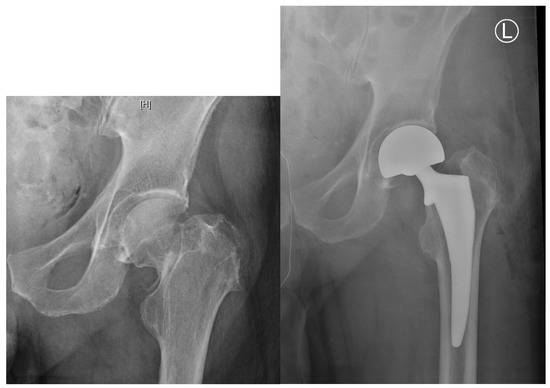

股骨颈内包含抗压与抗拉骨小梁,它们围成Ward三角。该三角上界为抗拉骨小梁,内下界为抗压骨小梁,是骨密度较低的区域(图1)。近期研究表明,骨小梁退化与股骨颈骨折发生密切相关,而Ward三角扩大则与股骨粗隆间骨折相关。

图1. (左)一位30岁女性患者的右髋X光片。(右)一位98岁男性患者的右髋X光片。注意右图中Ward三角(WT)的大小明显大于左图,并且与左图相比,右图中主要抗压骨小梁(A)和主要抗拉骨小梁(B)的退变更明显。